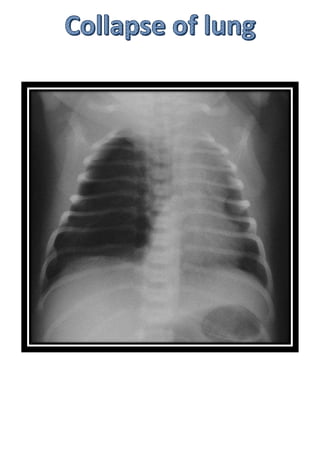

NECROTISING ENTEROCOLITIS

Stage 2 Definite NEC

Air enters intestinal wall

Divided into - iia: pneumatosis

intestinalis

AIR IN WALL

AIR IN LUMEN